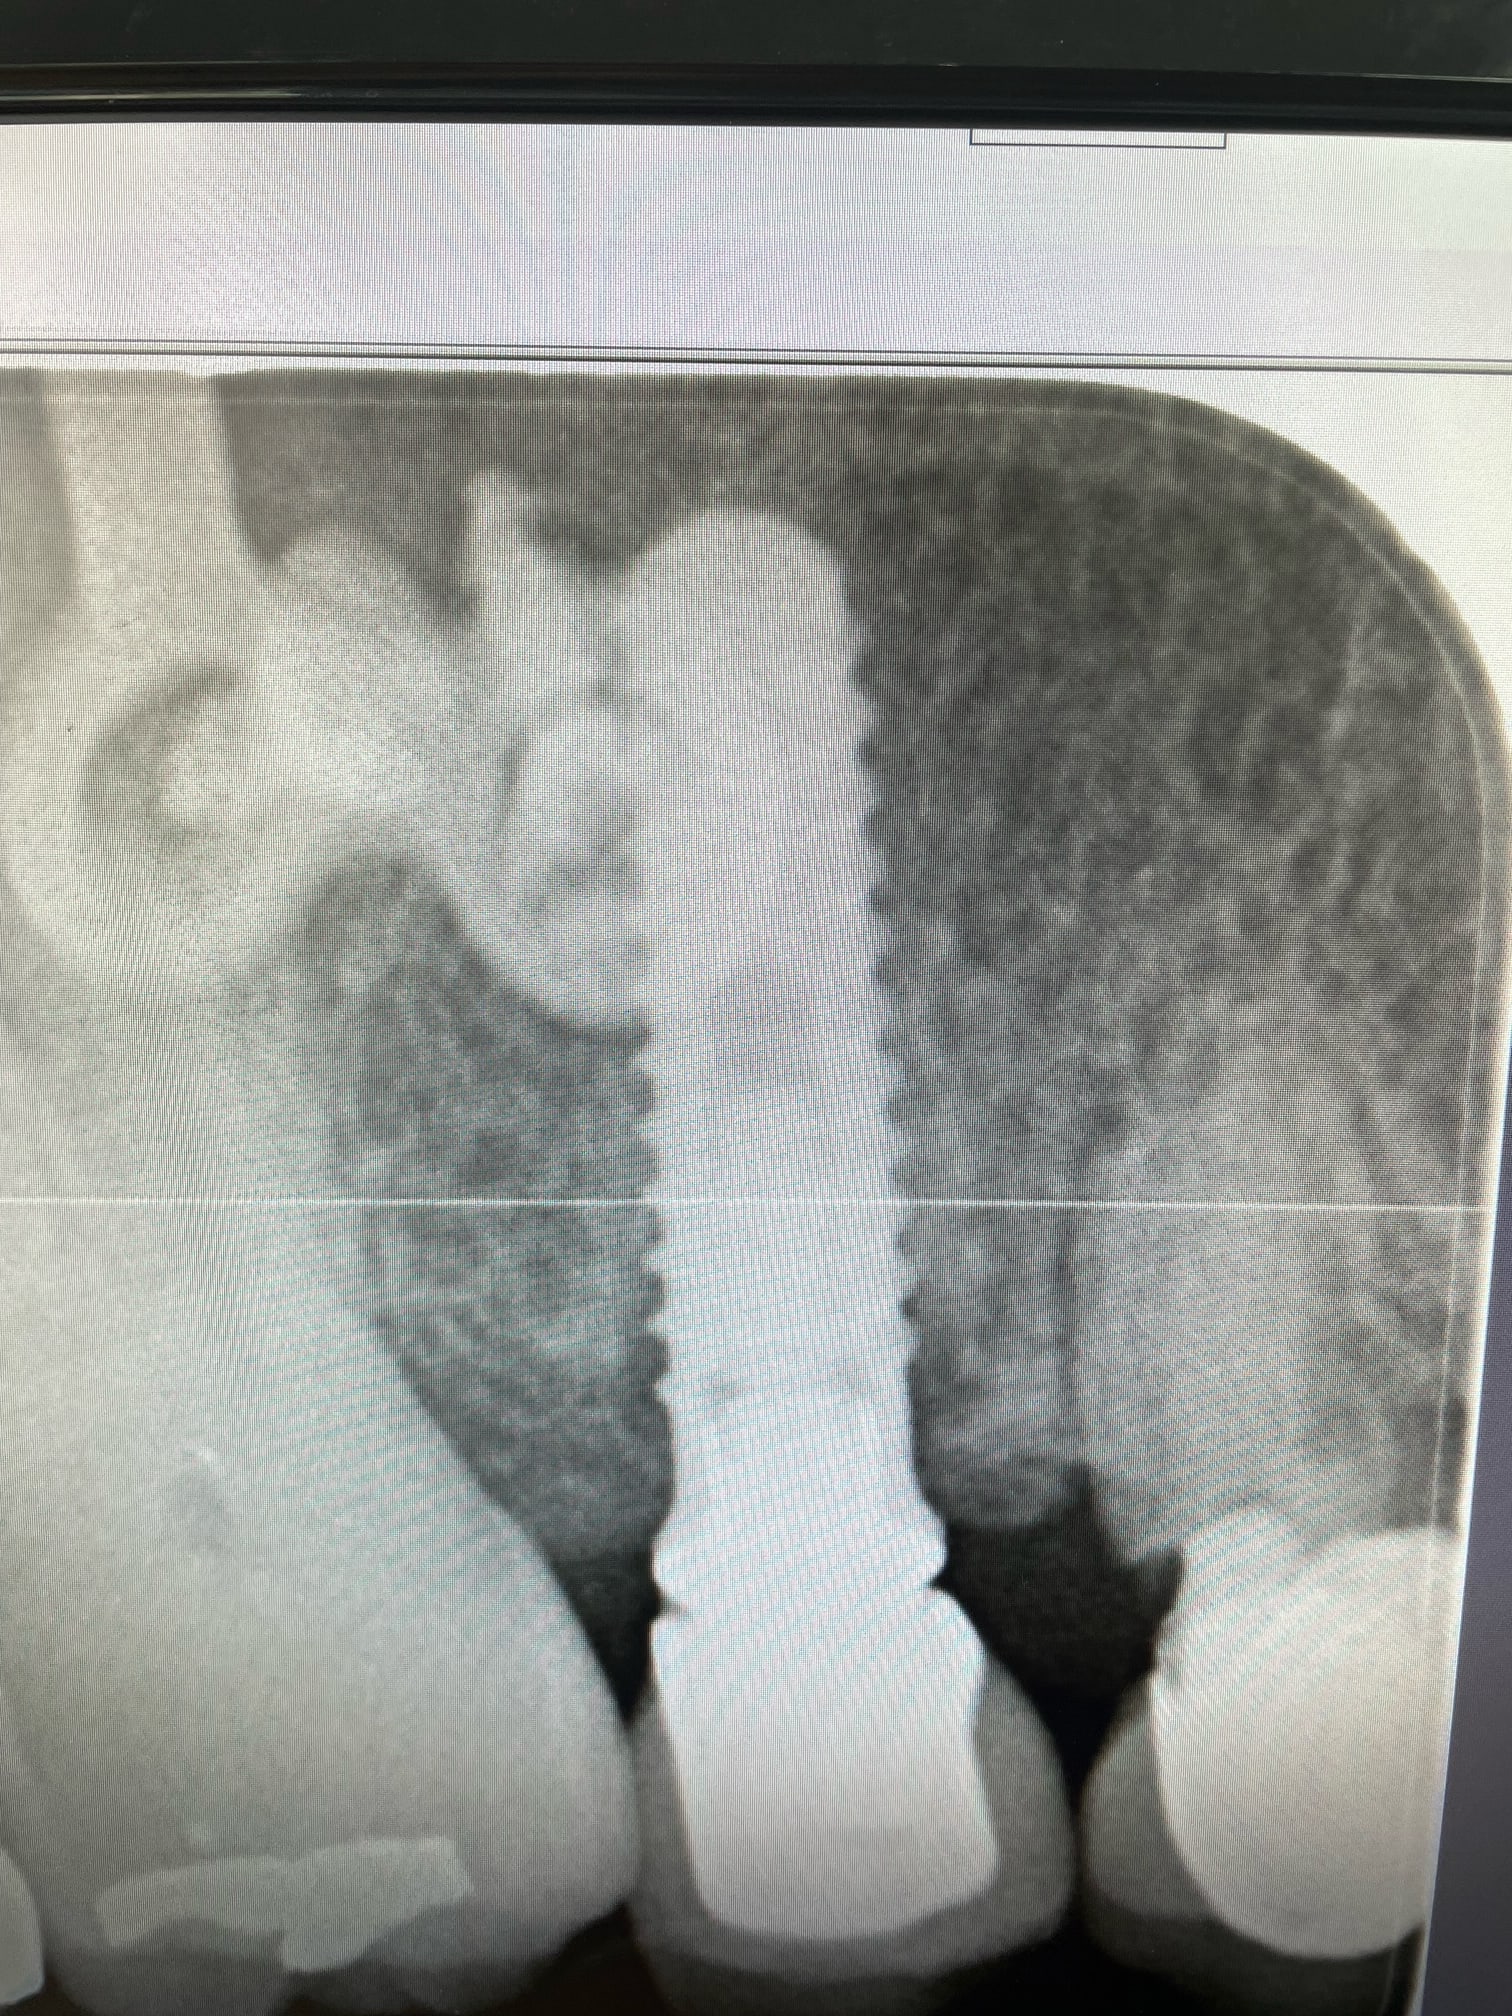

Bonjour, je cherche à confirmer que ces implants sont bien des IDI.

Si oui savez vous avec quelle marque ils sont compatibles et s’il existe des scanbody pour faire de l’empreinte optique?

Pas idi sur . Le seul ressemblant chez idi serait idmax mais il sont different sur plusieurs points

c'est clair.....l'idmax c'est celui qui se rapproche le plus sans cocher toutes les cases....c'est ce qui fait que j'ai pas l'impression que çà soit çà, car les spires semblent différentes.....et pour l'instant, je sèche....

Taille du col et régularité des spires

Des nouvelles de ma galère: les implants sont bien des IDI.

J’ai remis la main sur l’associé du poseur initial. Par contre ce sont des implants qui ont 15 ans. Peut être que la forme a évolué depuis. J’attends la traçabilité exacte la semaine prochaine.

Traçabilité définitive reçue ce matin: IDMAX 4,4. Y a plus qu’à !

Pense à commander l'ancien tournevis carré qui est beaucoup plus large que le plus récent... Et évidement le tournevis adéquat pour le nouveau pilier

Bon à savoir cette histoire de tournevis, merci!!